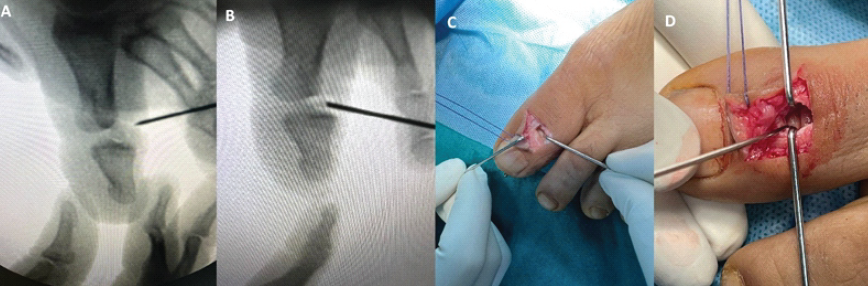

The IP joint of the left hallux was accessed through a dorsal L-shaped incision, as shown in Fig. 2. The extensor expansion was incised longitudinally to provide adequate exposure of the joint. Care was taken to preserve the surrounding soft-tissue structures.

Figure 2: These are the intraoperative clinical images showing an L-shaped dorsal incision with the medial flap retracted with the help of Vicryl suture.

Fluoroscopic evaluation confirmed a dorsal dislocation of the IP joint with an interposed sesamoid bone (Fig. 3a, b, c, d). On direct inspection, the sesamoid was visualized within the joint space, obstructing anatomical reduction.

Figure 3: These are the intraoperative clinical fluoroscopic and clinical images of an incarcerated sesamoid in between the interphalangeal joint of the great toe (a, b, c, d).